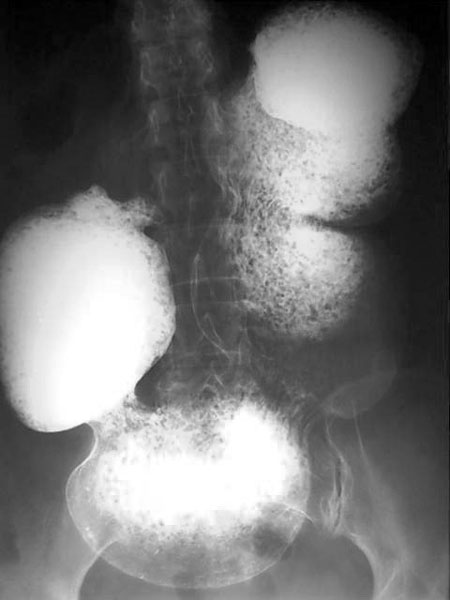

女,45岁,腹胀、腹痛不适数年,未扪及腹部包块。

胃下垂是肯定的,至于十二指肠球部有无问题则不好说,所给片子不全面!

胃的蠕动正常,好象不是低张造影!不是低张造影,胃的体积却这么大,为什么?感觉象是胃扩张,但不是急性的!胃的张力和蠕动正常,只是体积增大,我不支持胃下垂的诊断!!是什么,确实没有见过,静侯各位老师分析.....

支持胃下垂伴胃内大量潴留液,但要除外胃出口梗阻。

胃下垂伴胃内大量潴留液,小肠内无造影剂,提示幽门或十二直肠梗阻。

我认为胃下垂的诊断不应该只是一个胃大弯下界的位置改变,更重要的是胃张力和蠕动的改变.日常工作中瘦长体形的人胃的下界也很低,甚至底于髂骨上缘连线下5厘米,但是胃的排空和张力正常,并没有任何下垂症状,这样的患者我们如何能诊断为胃下垂??

胃下垂伴胃内大量潴留液,十二指肠球部似有变形,不除外球部溃疡所致!

胃腔扩大,内有潴留物,12指肠未见确切显影。胃扩张,考虑幽门或十二指肠梗阻。

胃下垂伴胃内大量潴留液,胃腔内小结节样低密度影,可能为服下的小颗粒状产气粉附着在潴留物上所致,小肠内无造影剂,提示幽门或十二直肠梗阻。